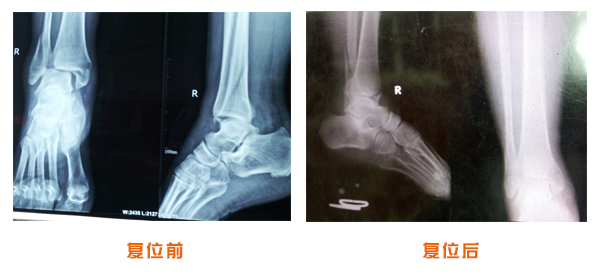

肥城市安駕莊梁氏骨科醫(yī)院是一所以梁氏手法正骨配合膏藥為特色的現(xiàn)代化專(zhuān)科醫(yī)院。

梁氏骨科術(shù)始創(chuàng)于清雍正年間,歷經(jīng)八代,至今已有三百年歷史。據(jù)1929年泰安縣志載“梁瑞圖先生,字增生,號(hào)蓮峰,安駕莊人,精岐黃并發(fā)明接骨,凡跌打車(chē)凡跌打車(chē)軋皮不破而碎骨者......【詳細(xì)】 |